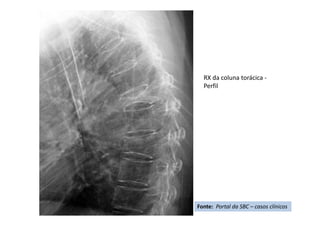

Radiografia

Ortostática de Perfil –

Pré operatória

• Cifose pós-traumática

• Resumo do caso: Queda da própria altura com diminuição de força de

membros inferiores de forma gradativa.

• Paciente (dados): Sexo feminino, 54 anos

• História: Queda da própria altura durante internação hospitalar em outro

serviço para tratamento de crise de ativação do LES há 6 meses. Apresentou

diminuição de força de membros inferiores de forma gradativa. Foi avaliada

no serviço de origem e realizado TC e aventada a hipótese de mielite

transversa. Foi encaminhada ao CRER para reabilitação. Nesse momento

apresentava apenas parestesia em MMII e FM grau 0 (ASIA B).

• Diagnóstico(s): Consolidação viciosa de T5, com cifose pós-traumática e

compressão medular (ASIA B)

• Antecedentes de Lúpus (LES), uso crônico de corticóide e tabagismo severo

• Tratamento(s): Realizada vertebrectomia com descompressão medular e

reconstrução com Mesh CAGE e artrodese de T2 a T8 por via posterior.

• Seguimento ("Follow up"): PO 1 ano com boa melhora funcional da

paciente.

• Resultado Final: Paciente apresentou melhora gradativa da força muscular e

da função, estando hoje com força muscular grau IV em MMII, conseguindo

deambular e inclusive subir e descer escadas com apoio (ASIA D).

Fonte: Portal da SBC – casos clínicos

RX da coluna torácica -

Perfil